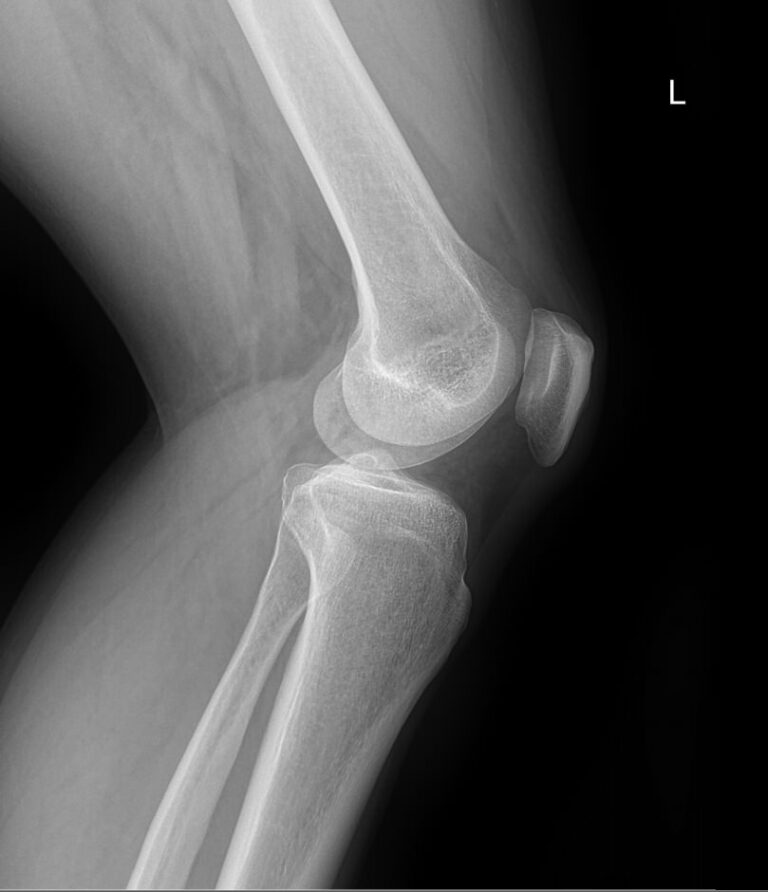

Назад Рентген обоих коленных суставов

Что покажет рентген обоих коленных суставов в одной проекции

В протоколе у каждого сустава описывается:

• Состояние мягких тканей;

• Суставная щель ― в норме, расширена, сужена, затемнена, имеет дополнительные включения;

• Состояние суставных  поверхностей и их соответствие друг другу ― несоответствие говорит о вывихе;

• Положение надколенника ― обычное или нет;

• Состояние костной ткани и надкостницы ― могут быть обнаружены участки разрежения, размягчения или других патологических процессов, а также свежие и сросшиеся переломы.